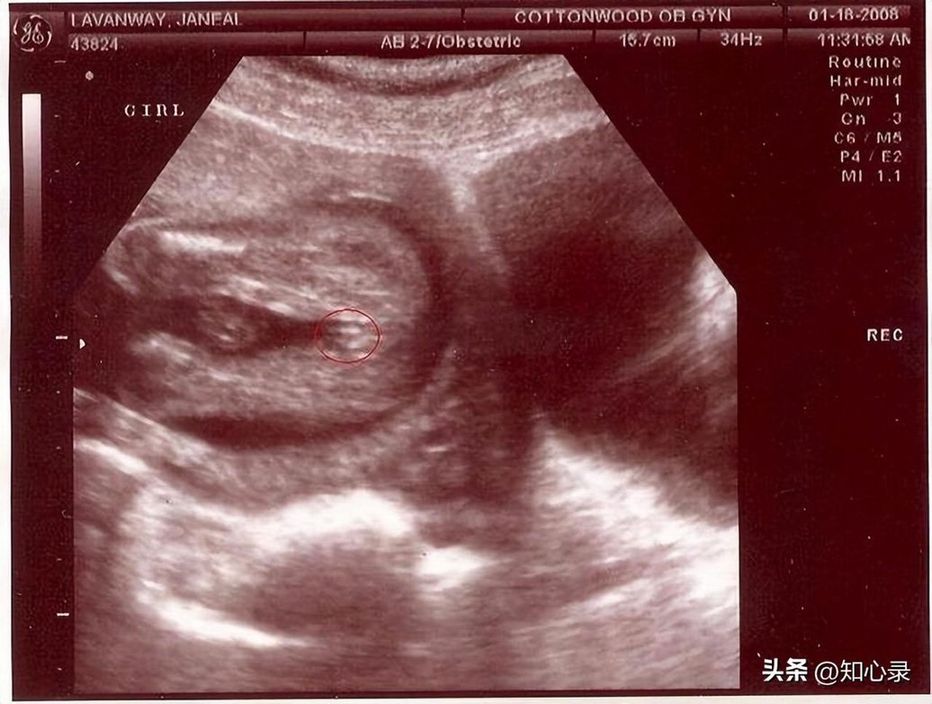

于是,工作人员带他们去看了孩子的B超。

看完以后,他们才敢相信这是真的。